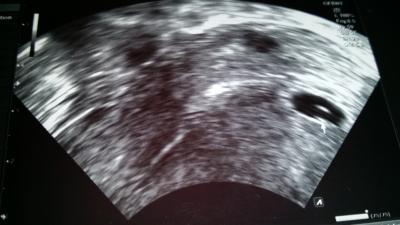

Ich war heute bei meinen Termien.Bin jetzt 5+2 .vielleicht sogar noch weniger weil mein eisprung so spät war.Also.... Fruchthöhle ist da ;-) und auch der Dozlttersack ist schon zu sehen.Bedeutet klein Würmchen ist auch da aber er ist noch so klein das er sich dahinter versteckt und man ihn noch nicht sehen kann.Arzt ist sehr zufrieden....weil man schon soviel sieht und alles gut entwickelt ist.In 2 Wochen am 28.07. Hab ich wieder Termien.bin dann in der 8ssw und dann muss man würmchen und herzschlag sehen. Uiiiiii bin soooo aufgeregt und sehr erleichtert.